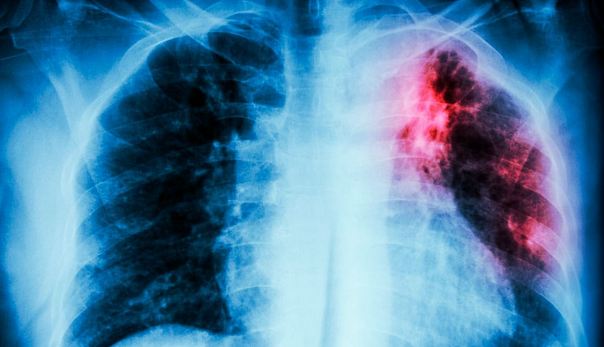

La tuberculosis es causada por una bacteria que afecta principalmente a los pulmones, aunque puede presentarse en otros órganos del cuerpo.

Sus síntomas más comunes incluyen tos persistente, en ocasiones con flema o rastros de sangre, pérdida de peso, fiebre, cansancio generalizado y sudoraciones nocturnas, de acuerdo con Sánchez Colín.

“Los síntomas de la tuberculosis dependen del órgano afectado. En el caso del tejido pulmonar, el paciente puede presentar tos crónica y productiva, lo que significa que arroja flema.

En algunas ocasiones, esta flema puede tener rastros o rayas de sangre. El paciente también puede desarrollar pérdida de peso, fiebre —principalmente nocturna— y sudoraciones durante la noche”.